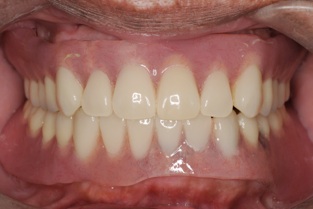

患者様も違和感がないと大喜びです。

もし、前歯が悪くなった場合、さらに2本インプラントを追加すれば固定式の歯をいれることができます。